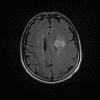

Neurologic and mental examination showed intact immediate memory but inability to recall 3 objects in 5 minutes. He was not oriented to time or space or situation but oriented to person. His remote memory was intact. There was left superior quadrantonopsia but no focal motor or sensory deficits. FLAIR images on MRI showed a lesion in the left mesial temporal lobe (Panel 1). This lesion had increased T2 signal but without enhancement on T1 images. This lesion also had mass-effect and edema within that region. On FLAIR images, there were some small foci of abnormal signal in the white matter of the right parietal lobe (Panel 2) but these foci did not enhance (Panel 3). There is a vague, poorly demarcated, triangular shaped periventricular signal abnormality in the left parietal lobe (Panel 2) but this area did not enhance (Panel 3). On another image (obtained higher to Panel 2 and 3), however, there is a small cluster of enhancing spotty signal in the white matter of the left parietal lobe (Panel 4) and the largest focus is about 0.4 cm in diameter. There were areas with features of encephalomalacia in his right mesial temporal lobe that would be explained by his history of prior infarct.

3. T1+Contrast |